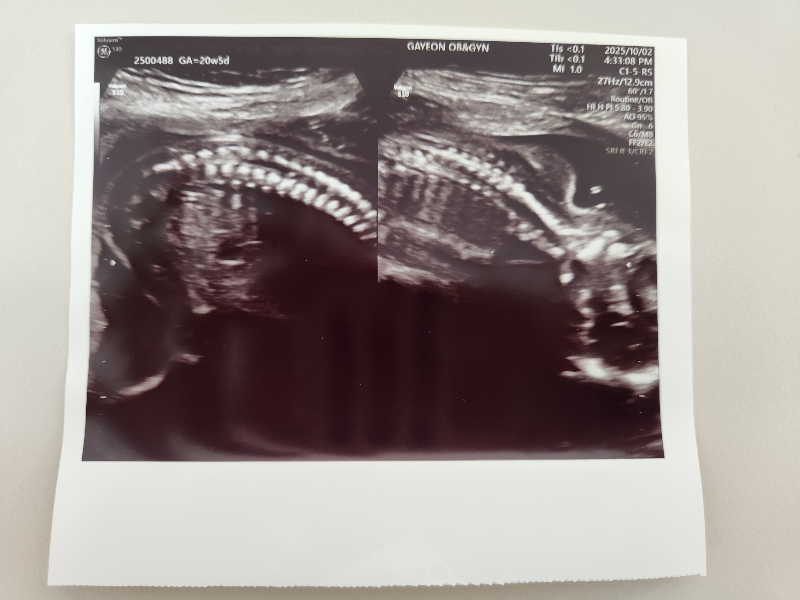

태아의 척추뼈도 확인합니다.